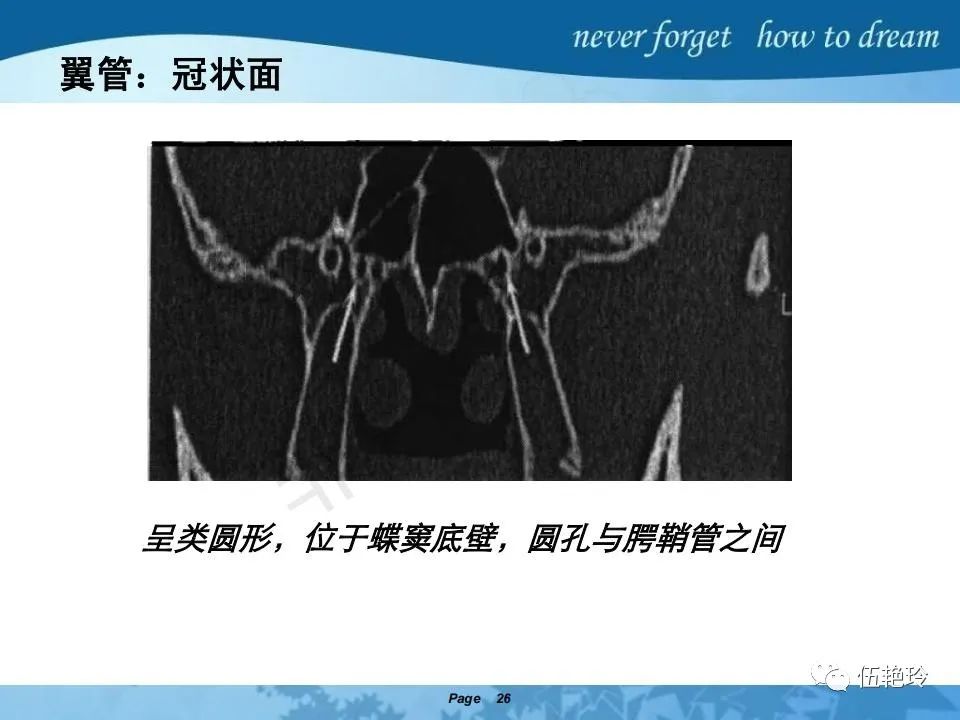

翼腭窝的解剖结构与鼻咽癌侵犯

2.31 向上颅内:①鼻咽顶壁→破裂孔(岩尖、斜坡)→蝶窦、海绵窦;②鼻咽顶壁→蝶骨基底部→蝶窦、海绵窦;③鼻咽侧壁→茎突前间隙→蝶骨大翼(卵圆孔)→海绵窦;④鼻咽侧壁→茎突前间隙→翼腭窝→ 颞下窝;⑤鼻咽前壁→鼻腔→翼突、翼腭窝→眶下裂→眶尖→海绵窦;⑥鼻咽前壁→鼻腔→上颌窦、筛窦;